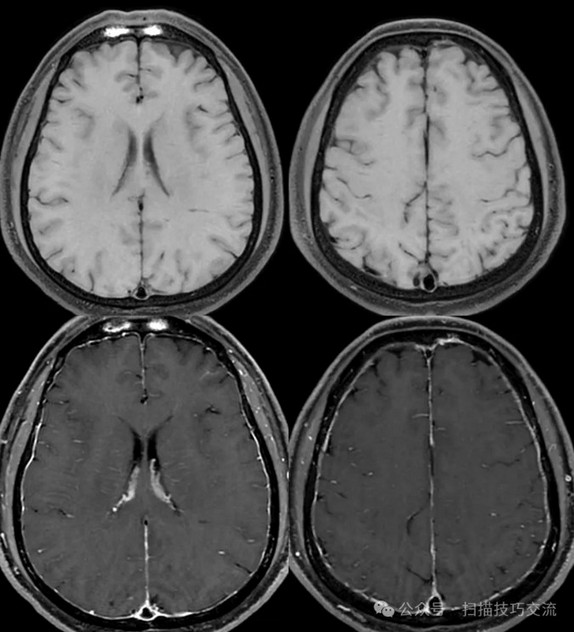

临床申请:颅脑平扫,静脉成像,磁敏感成像,颅内静脉血管黑血成像。

图像不逐一罗列,未见异常。